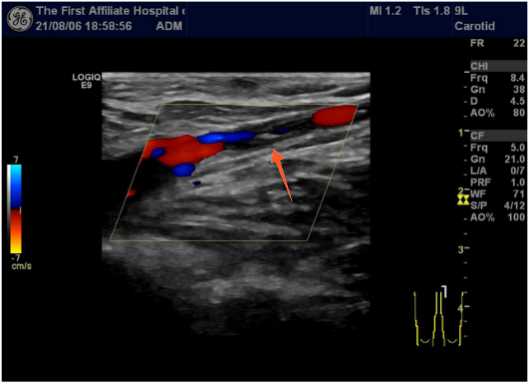

患者女,37岁,因“左下肢肿胀1天”于2021年07月10日入中山大学第一附属医院。中山大学第一附属医院下肢血管彩超提示双下肢静脉提示深静脉血栓形成,肺动脉CT可见双肺多发血栓形成(图1)。患者经抗凝溶栓治疗1个月后,于2021年08月04日出现大量阴道流血,并于2天后于家中昏迷,遂于2021年8月6日入暨南大学第一附属医院,诊断为子宫肌瘤。患者近期无外伤史、无输血史、无血液系统疾病史,无吸烟、吸毒史,近期无口服短效避孕药史,未婚未育,2年来有月经增多、经期延长、痛经史(月经周期28天,经期9~10天),体重正常,BMI 21.6 kg/m2。查体:生命体征平稳,贫血貌,宫底平脐上二横指,表面光滑,质硬,边界清,活动性差;双附件未触及。左下肢均匀凹陷性水肿,伴轻微疼痛,左下肢周径分别为左小腿39.5 cm (右侧37 cm),膝盖47 cm (右侧42.5 cm),大腿59 cm (右侧55.5 cm)。双下肢彩超提示:左侧大隐静脉根部及左侧股总、股浅、腘静脉血栓形成(图2)。B超提示:子宫体积增大,切面内径175 mm × 118 mm × 140 mm,实质回声欠均匀。内膜显示不清。宫腔内见一不均质低回声团,大小约117 mm × 146 mm × 117 mm,边界尚清。宫底肌层见一个实性低回声团,大小约44 mm × 56 mm × 48 mm,形状呈椭圆形,内部为低回声,分布均质,边缘清楚。盆腔MR提示:子宫后壁肌层见巨大类圆形异常信号影,大小约14.9 cm × 9.8 cm × 14.2 cm,病灶与子宫后壁肌层分界不清,增强扫描呈明显不均匀强化,考虑子宫平滑肌瘤与子宫平滑肌肉瘤相鉴别(图3)。血浆D-二聚体定量4270 ng/ml,血红蛋白HGB 61.30 g/L,蛋白S17.7%,抗磷脂抗体未见明显异常。入院后予缩宫素促进子宫收缩、促性腺激素释放激素激动剂(Gn-RHa)止血、生血宁纠正贫血、补液、输血、抗凝等对症处理后转介入科治疗血栓。于2021年8月16日行左下肢静脉造影 + 下腔静脉滤器植入术(图4)。DSA显示:左下肢股静脉、股总静脉上段、髂静脉、下腔静脉未见显影,股、髂静脉周围可见大量侧枝循环形成。术后予利伐沙班10 mg qd口服、升血宝15 ml tid + 红源达1片bid口服。患者病情稳定后复查CT示双肺肺动脉内多发血栓基本吸收,超声示肌瘤体积减小。遂于2021年8月30日在腰麻下行腹式子宫肌瘤剔除术,术中见子宫均匀增大如孕4月大小,质硬,表面光滑,宫底部见一带蒂浆膜下肌瘤,大小约60 mm × 50 mm × 50 mm。子宫及卵巢表面见炎性粘连带。术中病理冰冻结果:子宫平滑肌瘤伴玻璃样变性。手术顺利,两个肌瘤(总重量约900 g)在手术中被完全切除,未穿透子宫腔,术中出血约500 ml,患者未诉特殊不适。术后常规预防感染,低分子肝素抗凝治疗,复查患者血浆d-二聚体浓度降至670 ng/ml。术后4天取出下腔静脉滤器,患者活动后无不适出院,予利伐沙班口服半年预防血栓复发,并予Gn-RHa连续治疗3个周期,定期随访有无新发血栓形成。

Figure 2. Color ultrasound of both lower limbs: thrombosis of the left saphenous vein root and the left common femoral, superficial femoral and popliteal veins

2. 双下肢彩超:左侧大隐静脉根部及左侧股总、股浅、腘静脉血栓形成